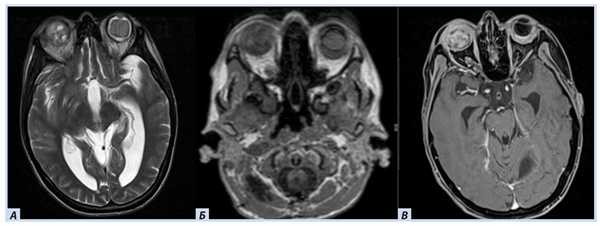

Лучевые методы. На МРТ-изображениях головного мозга выявлено характерное двустороннее поражение глаз (рис. 1), по данным КТ — с участками обызвествления (рис. 2). Также на КТ головного мозга были выявлены зона послеоперационных кистозно-глиозных изменений с наличием кисты и узла на уровне посттрепанационного дефекта в правом полушарии мозжечка, а также аналогичные зоны дорзальнее и в субкортикальных отделах; в левой гемисфере мозжечка определялись кистозные изменения (рис. 3).

Рис. 1. Пациентка П., 30 лет, с диагнозом «Болезнь Гиппеля−Линдау»: магнитно-резонансная томография головного мозга

Примечание. А, Б — Т2- и Т1-взвешенные изображения. В полости правой глазницы объемное образование с неоднородным МР-сигналом; В — постконтрастное Т1-взвешенное изображение, режим подавления сигнала от жира: определяется интенсивное, но гетерогенное контрастирование образования. Кровоизлияние в сетчатку справа.

Рис. 3. Пациентка П., 30 лет, с диагнозом «Болезнь Гиппеля−Линдау»: магнитно-резонансная томография головного мозга

Примечание. А — Tirm-режим: на фоне кист мозжечка визуализируется мягкотканный компонент, прилегающий к кисте справа; Б — DWI-режим: зона рестрикции диффузии по ходу стенки кисты справа; В — постконтрастное Т1-взвешенное изображение, режим подавления сигнала от жира: в той же зоне отмечается накопление.

В спинном мозге больной на уровне шейного отдела были выявлены кистозные полости с узлами гемангиобластом (рис. 4).

Рис. 4. Пациентка П., 30 лет, с диагнозом «Болезнь Гиппеля−Линдау»: магнитно-резонансная томография спинного мозга

Примечание. А — постконтрастное Т1-взвешенное изображение, режим подавления сигнала от жира: отмечается узел (гемангиобластомы) с аккумуляцией гадолинийсодержащего контраста; Б — Tirm-режим: на фоне кист спинного мозга визуализируется мягкотканный компонент, краниально прилегающий к кисте.